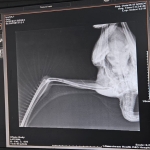

Kent içerisinde yaralı, hasta ve bitkin halde görülen hayvanları tedavi edip sağlığına kavuşturan Osmangazi Belediyesi, son olarak bir leyleği yaşama döndürdü. Nilüferköy Mahallesi’nde yer alan Merkez Cami’nin içerisine uçamayan bir leylek girdiği yönünde ihbar alan Osmangazi Belediyesi Veteriner İşleri Müdürlüğü ekipleri, hazırlıklarını yaparak adrese gitti. Caminin içerisinde bulunan leyleğin yanına giden ekipler, leyleği yakalayarak ilk müdahaleyi orada yaptı. Ekipler, sağlık durumu hakkında detaylı bilgi sahibi olmak ve gerekli muayeneyi uygulamak adına yaralı leyleği Sahipsiz Hayvanlar Doğal Yaşam ve Tedavi Merkezi’ne götürdü. Veteriner hekim tarafından sağlık kontrolü yapılan ve röntgeni çekilen leyleğin, kanadında darbeye dayalı yaralanma olduğu ve bu yüzden uçamadığı tespit edildi. Yapılan medikal tedavinin ardında birkaç gün içerisinde sağlığına kavuşması beklenen leylek, Büyükşehir Belediyesi Hayvanat Bahçesi’ne teslim edildi.